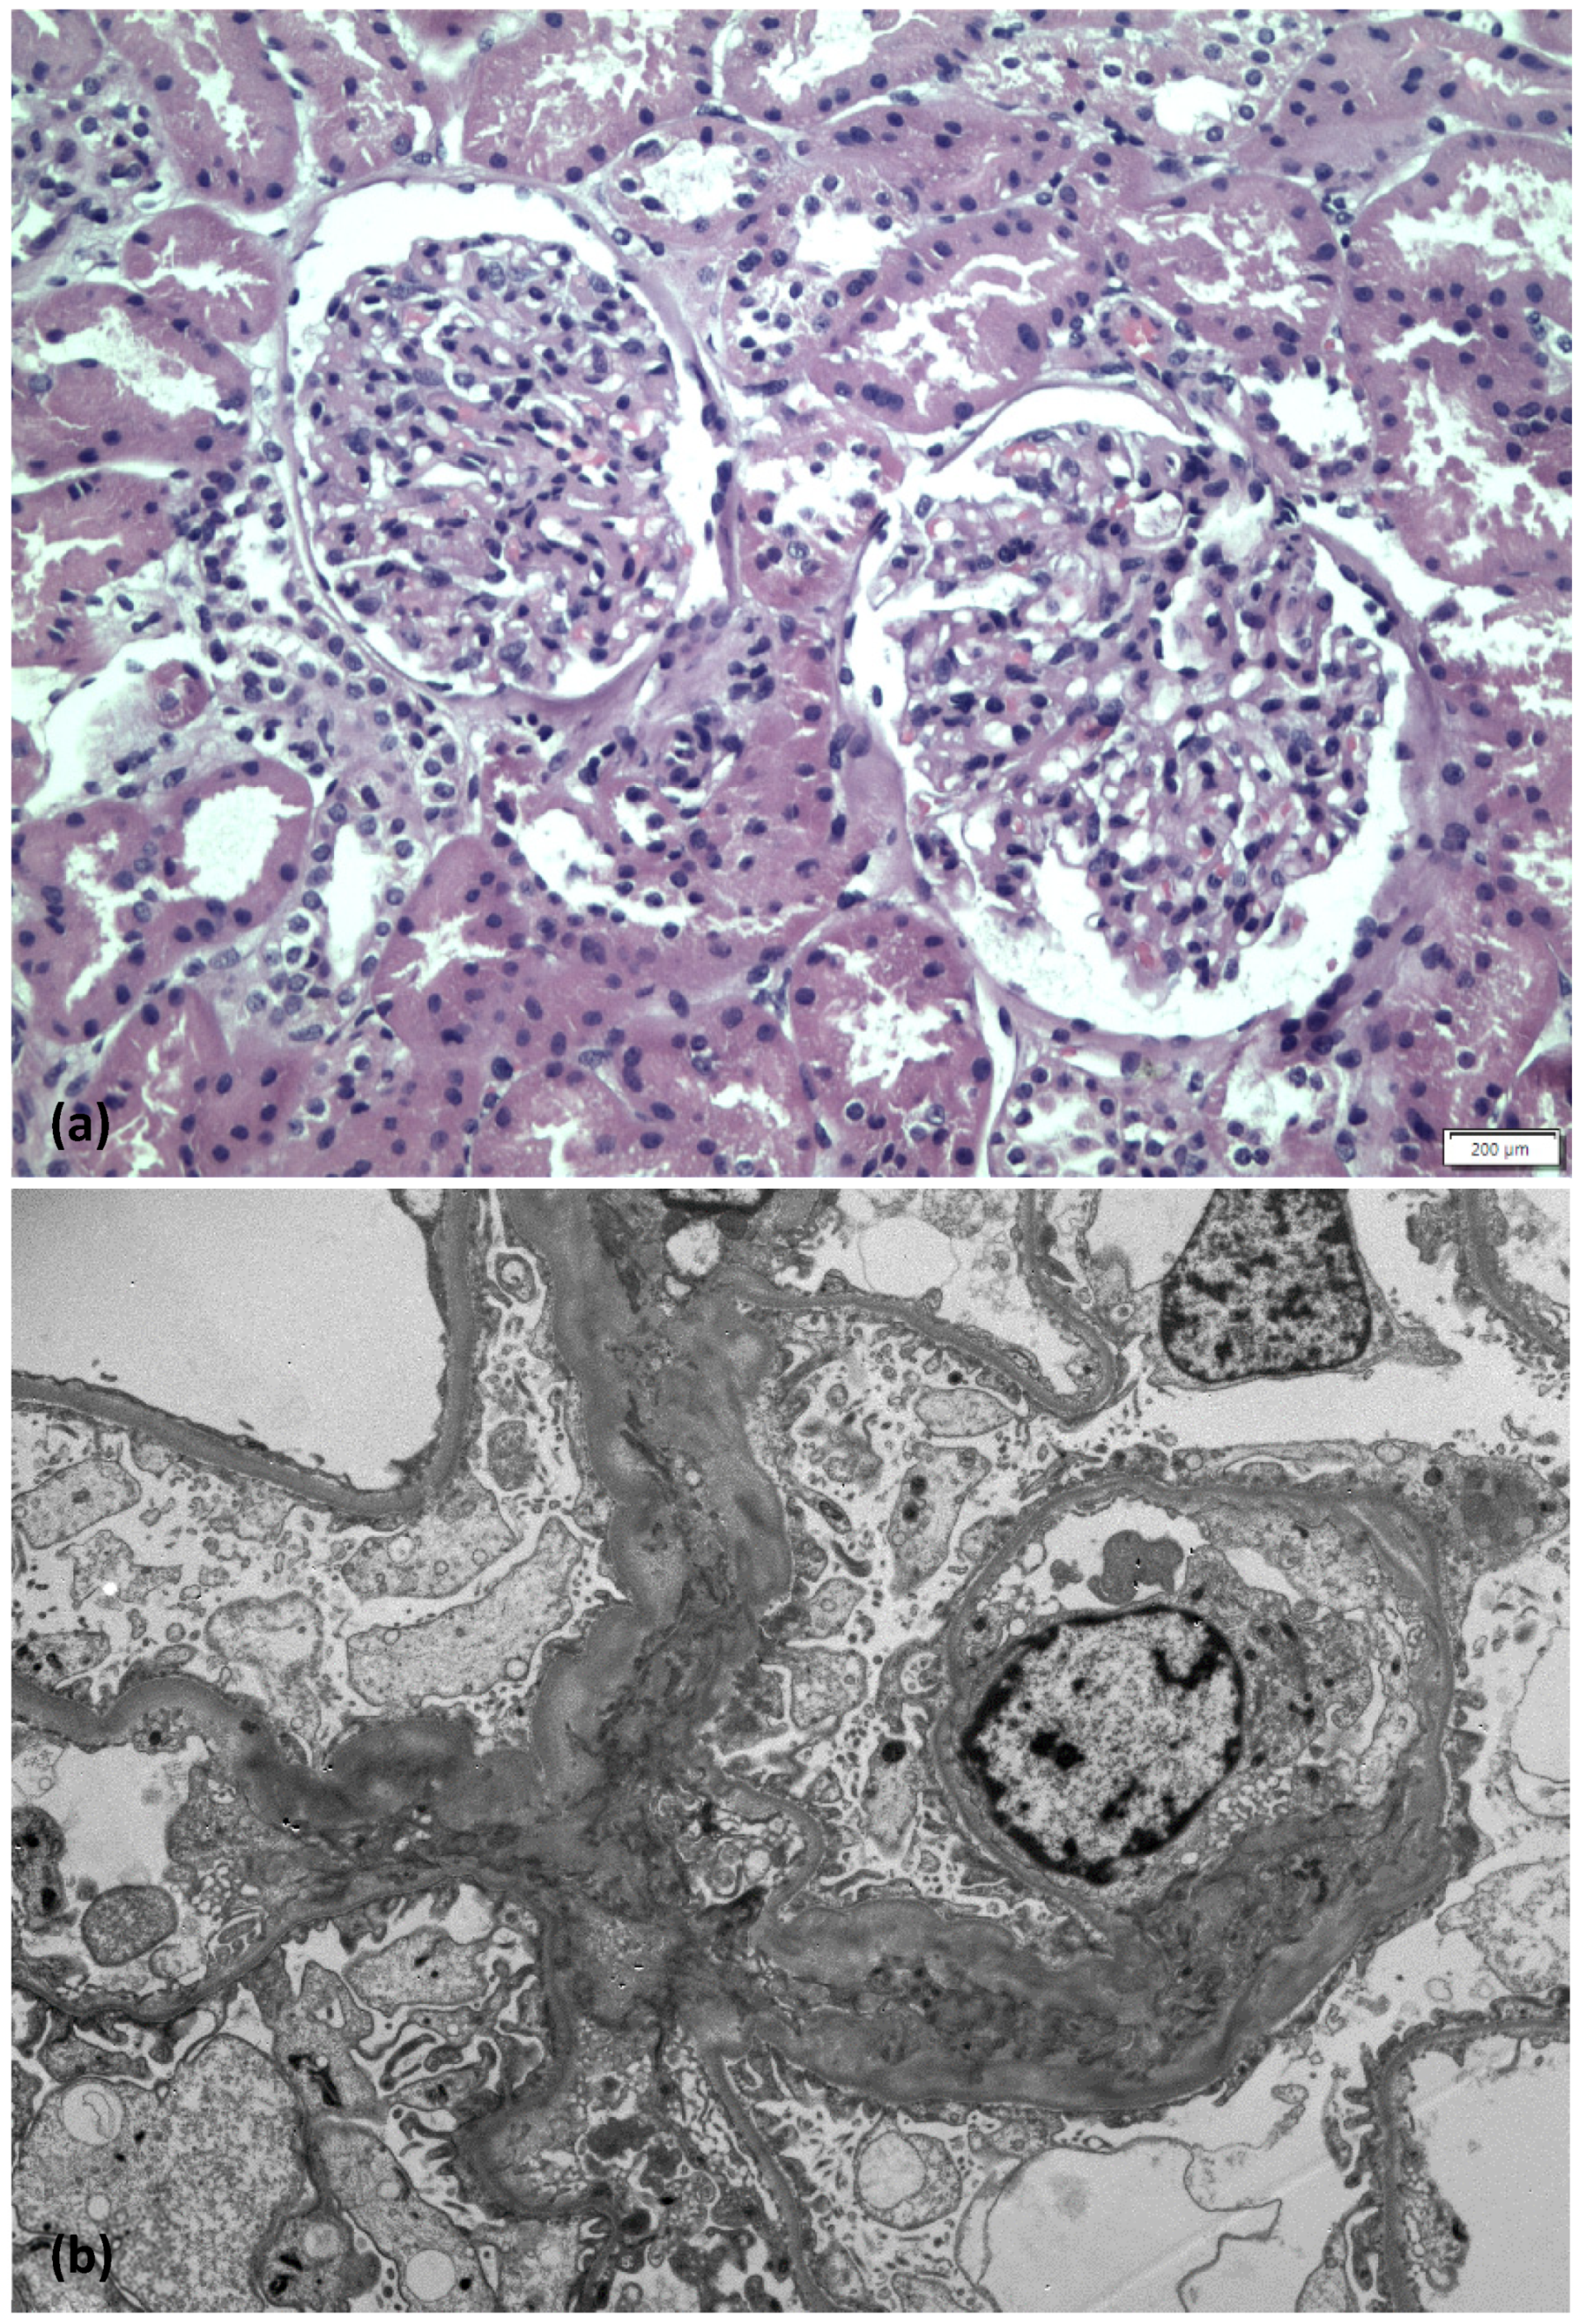

On light microscopy, 25 glomeruli were identified—three of them with global sclerosis. Glomeruli appeared unremarkable; focally mild mesangial expansion was present. Tubular atrophy and interstitial fibrosis were mild, while vessels exhibited mild to moderate arteriosclerosis. Immunofluorescence examination revealed no immune deposits. Accordingly, on electron microscopy examination, no electron dense deposits were found, while diffuse foot process effacement with microvillous transformation was demonstrated (Figure 2). The final diagnosis was consistent with minimal change disease.

Figure 2. Images from light microscope (a), electron microscope (b).